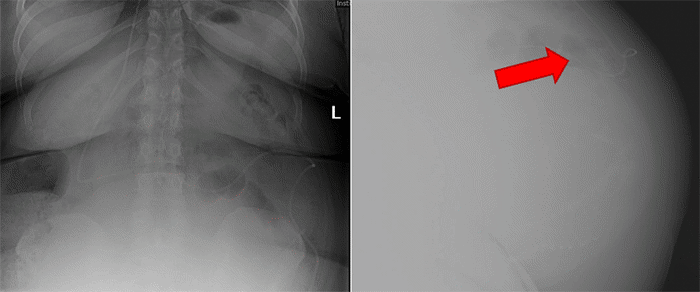

She initially presented to the emergency department twice within a two-week period. The initial presentation was for intractable headaches. A head computed tomography (CT) ruled out hydrocephalus, and an X-ray shunt series showed an intact VP shunt catheter (Figure 1). Despite these findings, she was discharged home after two days. However, headaches persisted upon discharge, accompanied by new symptoms of epigastric abdominal pain and diarrhea. The night prior to presentation, triggered by the sensation of something protruding from her anus during a bowel movement, physical examination revealed a tender epigastric region but no signs of peritonitis or meningitis. The examination also identified the peritoneal end of the VP shunt visibly protruding through the anus, as seen in Figure 2.

Figure 1. VP Shunt Series Demonstrating Appropriate Catheter Position. Published with Permission

Figure 2. Anal Protrusion of VP Shunt Catheter. Published with Permission

While physical examination showing the VP catheter protruding is often diagnostic, various imaging modalities can be used as supplemental tools. Abdominal X-rays, CT scans, and endoscopy have all been described as helpful adjuncts in the diagnosis.4 However, studies by Shuiab et al. have highlighted the low diagnostic yield of the VP shunt X-ray series in detecting clinically significant shunt malfunctions. Their research found a low sensitivity (18.7%) and positive predictive value (13%) for this modality.17 The authors concluded that using this diagnostic modality prolonged turnaround time, increased medical costs, and unnecessary radiation exposure for patients. Utilizing the patient's symptomology and CT scans should be the preferred diagnostic modality.17 Notably, in our case, a VP shunt series performed two weeks prior to presentation failed to identify the complication.